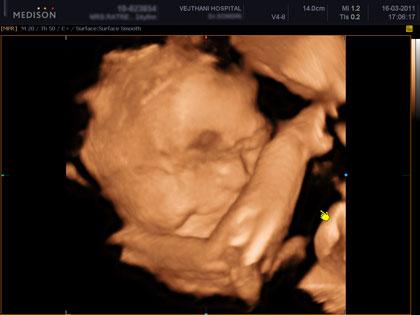

อัลตราซาวด์ 4 มิติ คือการอัลตราซาวด์ 4 มิติ ส่วนใหญ่ก็จะใช้ดูโครงสร้างของเด็ก ดูความผิดปกติ รวมทั้งสามารถดูสีหน้าท่าทางของทารก ซึ่งเป็นอาการตามธรรมชาติของทารก นอกจากนี้ก็ยังสามารถดูโรคที่เป็นความพิการทางโครงสร้าง เช่น ปากแหว่งเพดานโหว่ หัวใจพิการอย่างรุนแรง กะโหลกศีรษะ เป็นต้น ไม่ว่าจะเป็นอวัยวะภายนอกหรือภายใน ก็สามารถดูได้ทั่วทั้งร่างกายของทารก รวมไปถึงการตรวจวัดขนาดของทารก ทั้งนี้จะเป็นประโยชน์อย่างมากกรณีที่พบว่าทารกมีความผิดปกติ แพทย์สามารถวางแผนการรักษาหลังคลอดได้ล่วงหน้า ว่าจะรักษาอย่างไรต่อไป ซึ่งจะทำให้ทารกได้รบการรักษาในทันที

คลิปภาพทารกจากอัลตราซาวด์ 4 มิติ